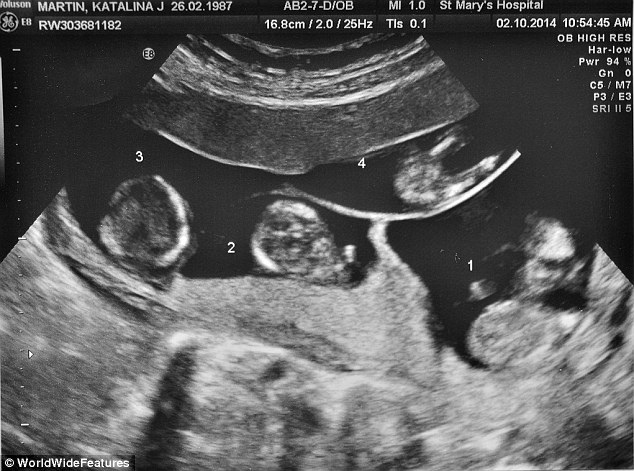

(Dân trí) - 4 em bé ra đời cùng lúc là khá hiếm gặp nhưng trường hợp của các bé Amelia, Sofia, Aston và Roman còn hi hữu hơn nữa, vì không những được thụ thai tự nhiên, mà các bé còn đến từ 4 trứng khác nhau. Đây được xem là ca sinh 4 chưa từng có ở nước Anh.

Mỗi năm ở anh chỉ có 3 - 4 trường hợp đẻ sinh tư. Những trường hợp này thường xảy ra khi có 1 hoặc 2 trứng được thụ tinh phân chia trong tử cung của người mẹ. Có nghĩa là sẽ có từ 2 đến 3 bé trong số 4 em là từ một trứng. Thậm chí những em bé này có thể gồm 2 cặp sinh đôi cùng trứng.

Các chuyên gia cho biết họ chưa từng nghe nói về trường hợp nào sinh tư không cùng trứng được thụ thai tự nhiên chứ không phải thụ tinh trong ống nghiệm.

Martin nhập viện St Mary khi được 27 tuần và 4 bé chào đời nhờ mổ đẻ 3 tuần sau đó, vào tháng Hai. Sofia nặng 1.700g, Roman nặng 1.250g, Aston 1.400g và Amelia 1.550g.